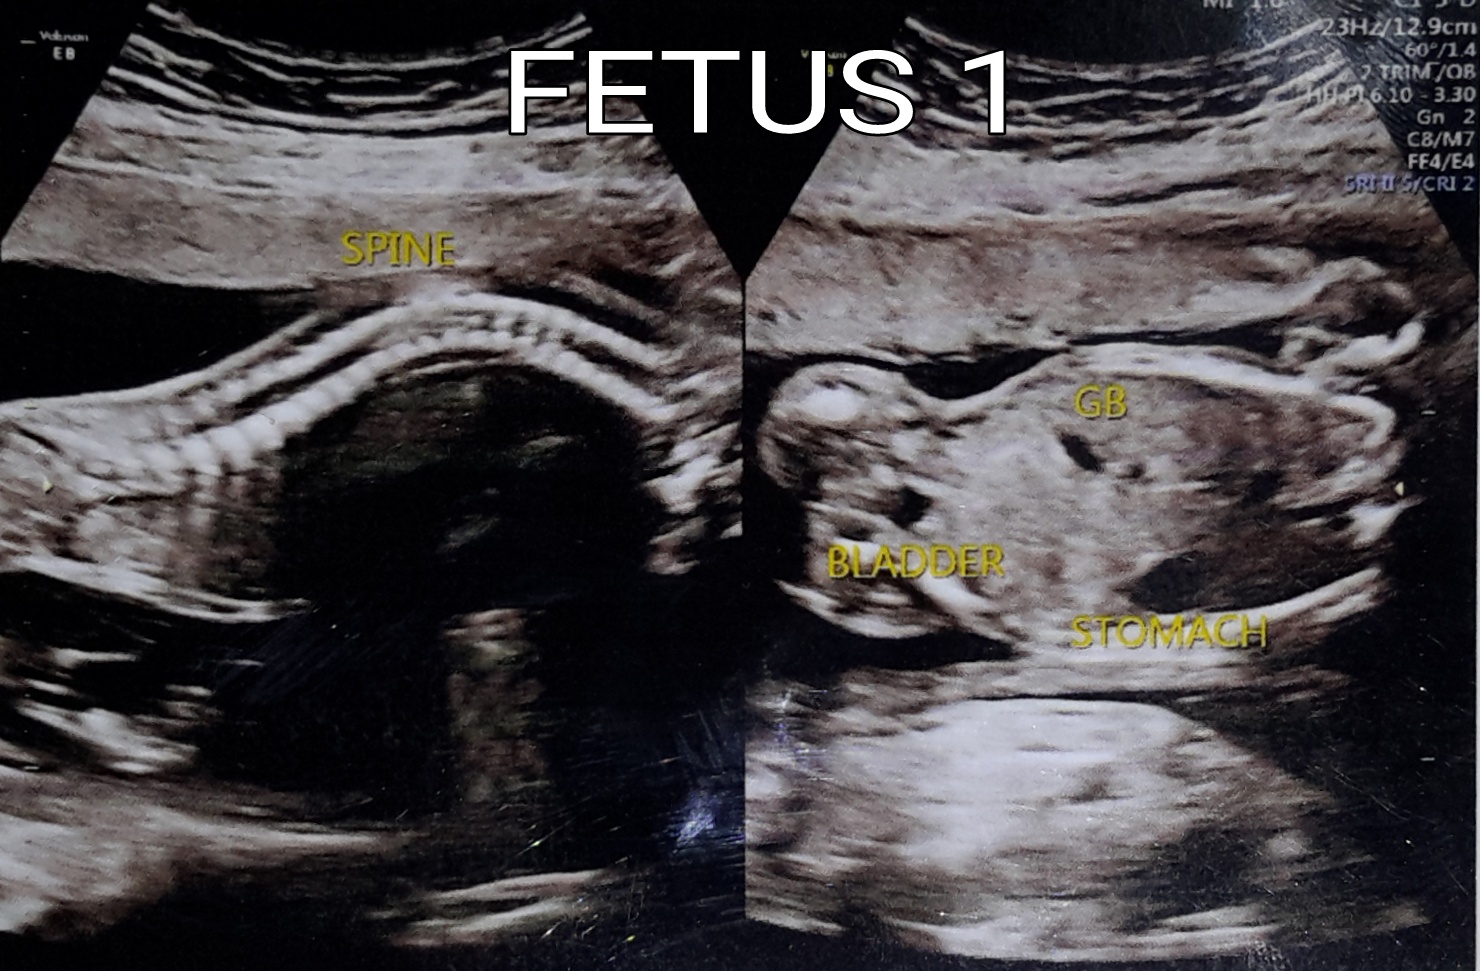

I just got my 19 weeks ultrasound. I am having fraternal (non identical) twins.

Any guesses please?